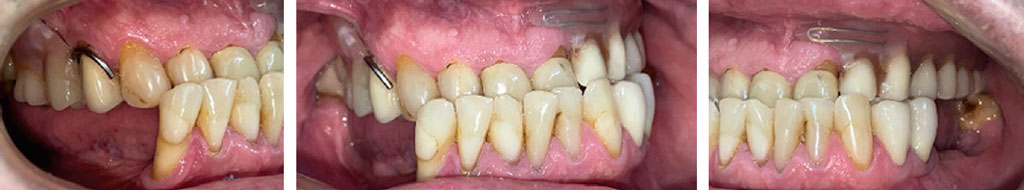

Произведено препарирование зубов под искусственные коронки (рис. 10).

Рис. 10. Зубы, обработанные под искусственные коронки

Fig. 10. Teeth prepared for crowning